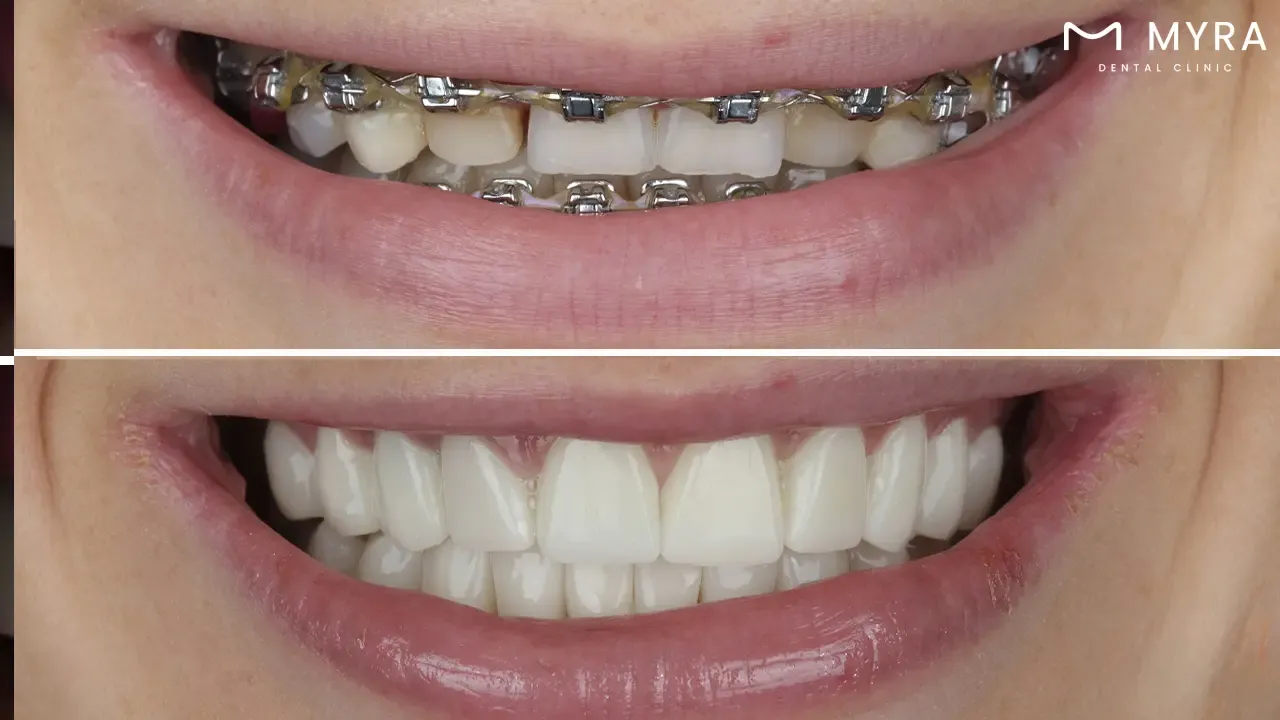

Orthodontic procedures: Orthodontic procedures are employed to straighten the teeth and enhance the overall alignment of the smile, braces, clear aligners, or others.

4.Orthodontics

A person's self-confidence and general well-being are increased by having a smile that sparkles and straight teeth, in addition to other benefits for overall dental health. it is simpler to chew food and talk clearly after undergoing the procedure to improve the function of the teeth and bite so, what is orthodontics? A specialist area of dentistry and orthodontics is concerned with the identification, avoidance, and correction of dental and skeletal anomalies. The Greek terms "ortho," which means straight, and "odont," which means tooth, are the origin of the word "orthodontics."

Orthodontists are dentists who have completed an additional 2–3 years of specialised study after dental school to become experts in resolving dental misalignments, bite disorders, and other associated problems. Orthodontists employ a range of instruments and methods, like braces, aligners, and retainers, to straighten teeth and enhance oral health in general.

Orthodontic therapy is crucial for preserving good dental health in addition to making smiles more aesthetically pleasing. The risk of tooth decay, gum disease, and other oral health issues rises due to the difficulty of cleaning crooked teeth. Additionally, headaches, jaw pain, and other discomforts are brought on by biting issues.

Orthodontic treatment starts at any age, but most doctors prescribe it for kids between 8 and 14. Early intervention helps resolve problems before they worsen and become more difficult to cure. Adults benefit from orthodontic treatment, and several choices are meant to be unobtrusive and comfortable.